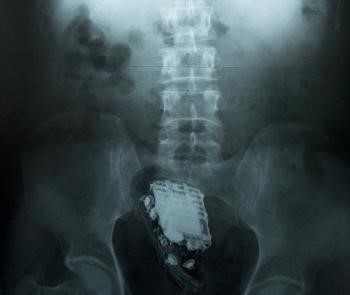

- ▲ ⓒ공개된 죄수의 엑스레이 사진 중.

발각 직후 죄수는 인근 병원으로 후송됐으며 의사들이 진땀을 흘리며 무사히 직장 속에서 휴대전화를 빼내는데 성공했다고.